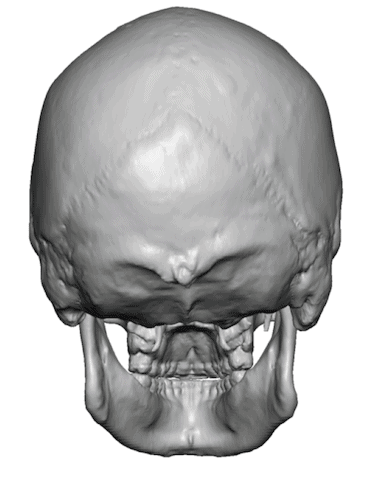

Desire for rounder shape to the top of the head from a congenital parasagittal deficiency skull shape.

Custom skull implant designed to fill in the parasagittal deficiencies.

Desire for rounder shape to the top of the head from a congenital parasagittal deficiency skull shape.

Custom skull implant designed to fill in the parasagittal deficiencies.